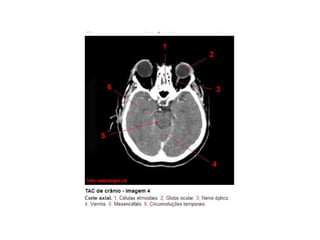

Anatomia E Protocolo Tomografia Computadorizada de Crânio PPT

Anatomia Seccional do Crâneo em Tomografia Computadorizada PPT